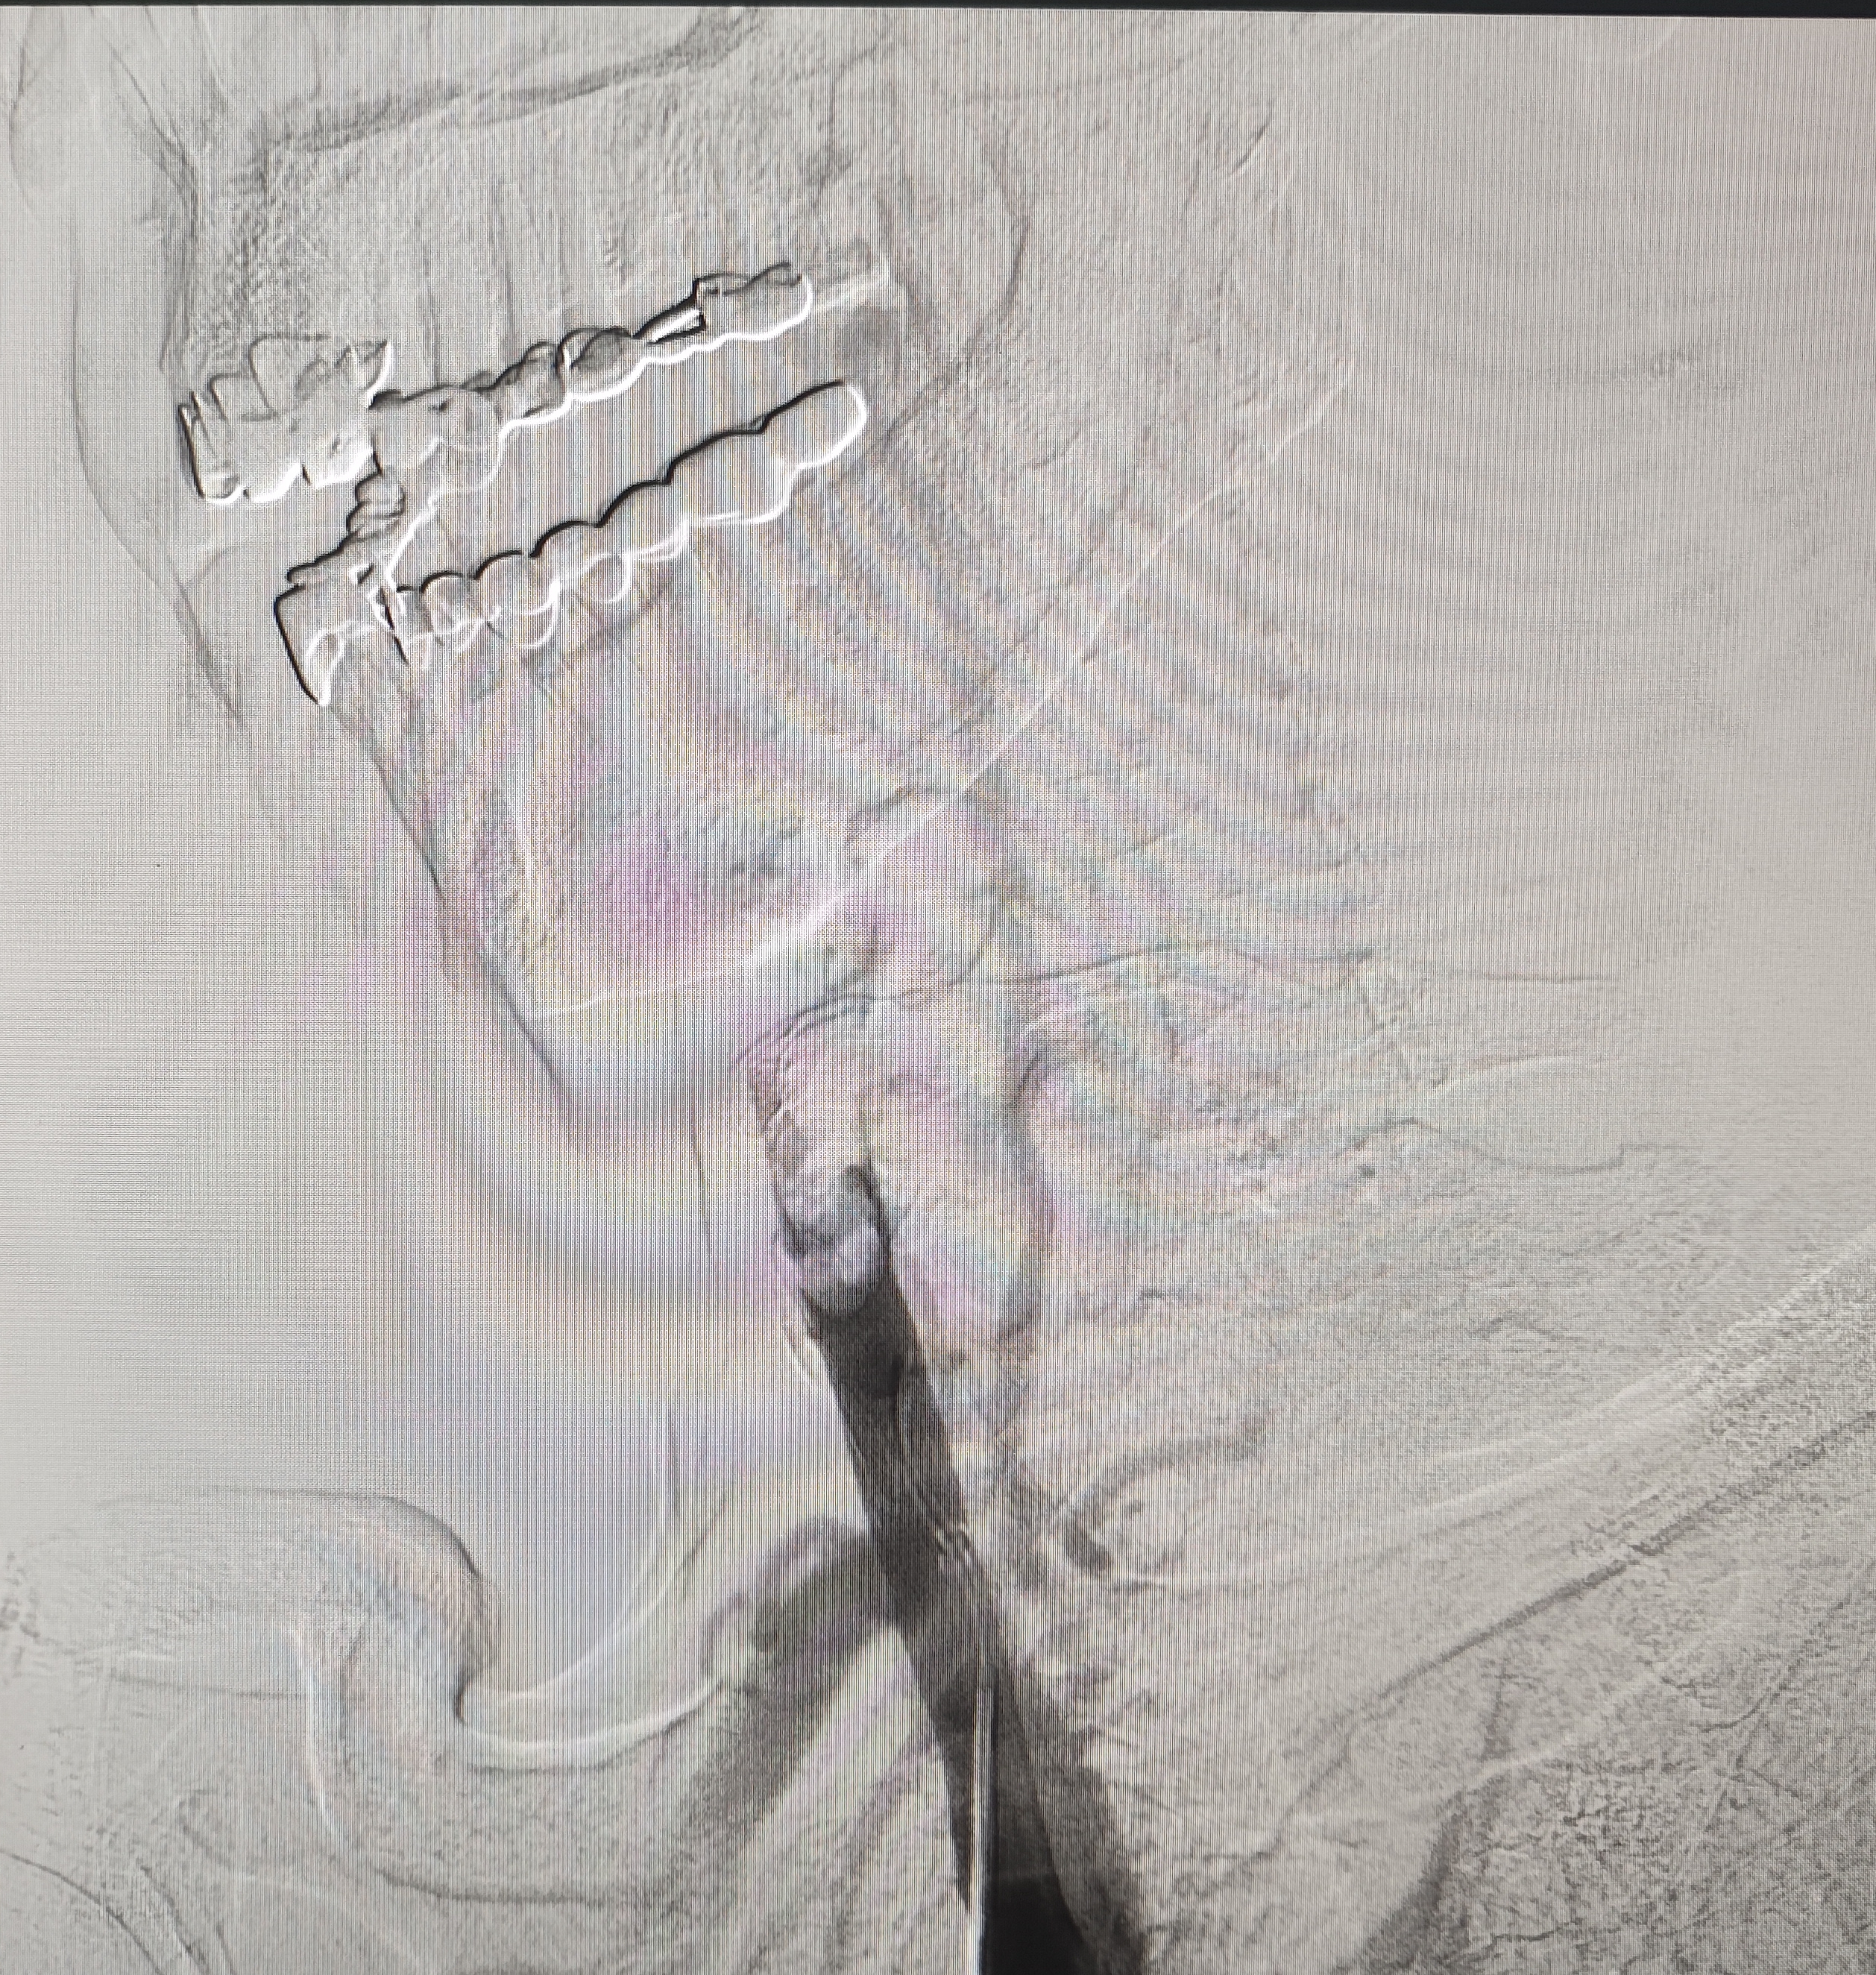

颈总巨大斑块急性闭塞的血管内治疗(双颈动脉支架桥接+支架释放后掉斑块,抽吸取栓)

急诊上台。